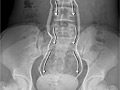

- An intravenous pyelogram (IVP). This is an X-ray test that shows pictures of the urinary tract and kidney stones.

- An abdominal X-ray (KUB). This creates a picture of the kidneys, the bladder, and the tubes that connect the kidneys to the bladder (ureters).